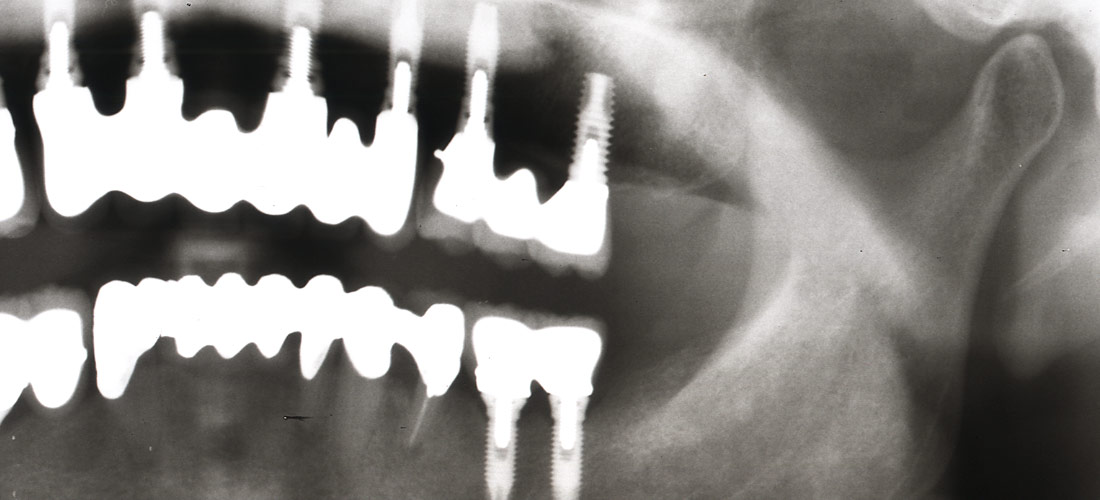

根管治療 → エクストゥルージョン

左上7部違和感で来院。

術前写真

比較的最近治療されたそうですが、クラウンの下に何やら影が、、、、、、、